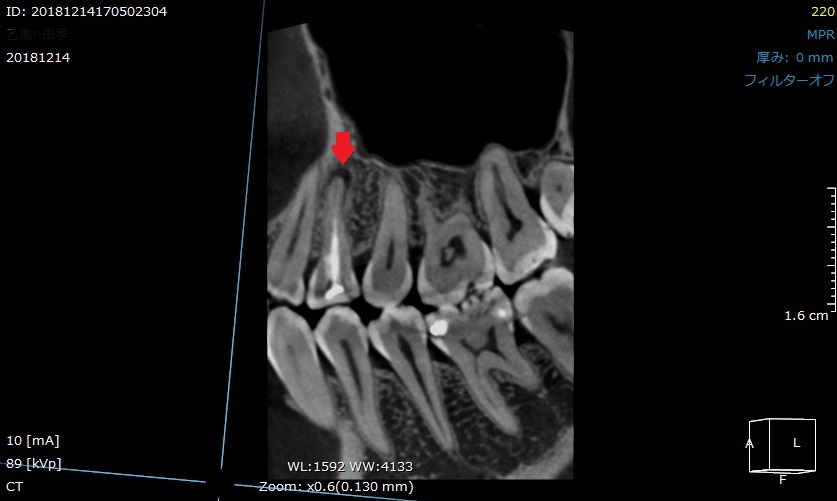

「歯を抜かないといけない」と言われたが、当院で抜かずに終えました。